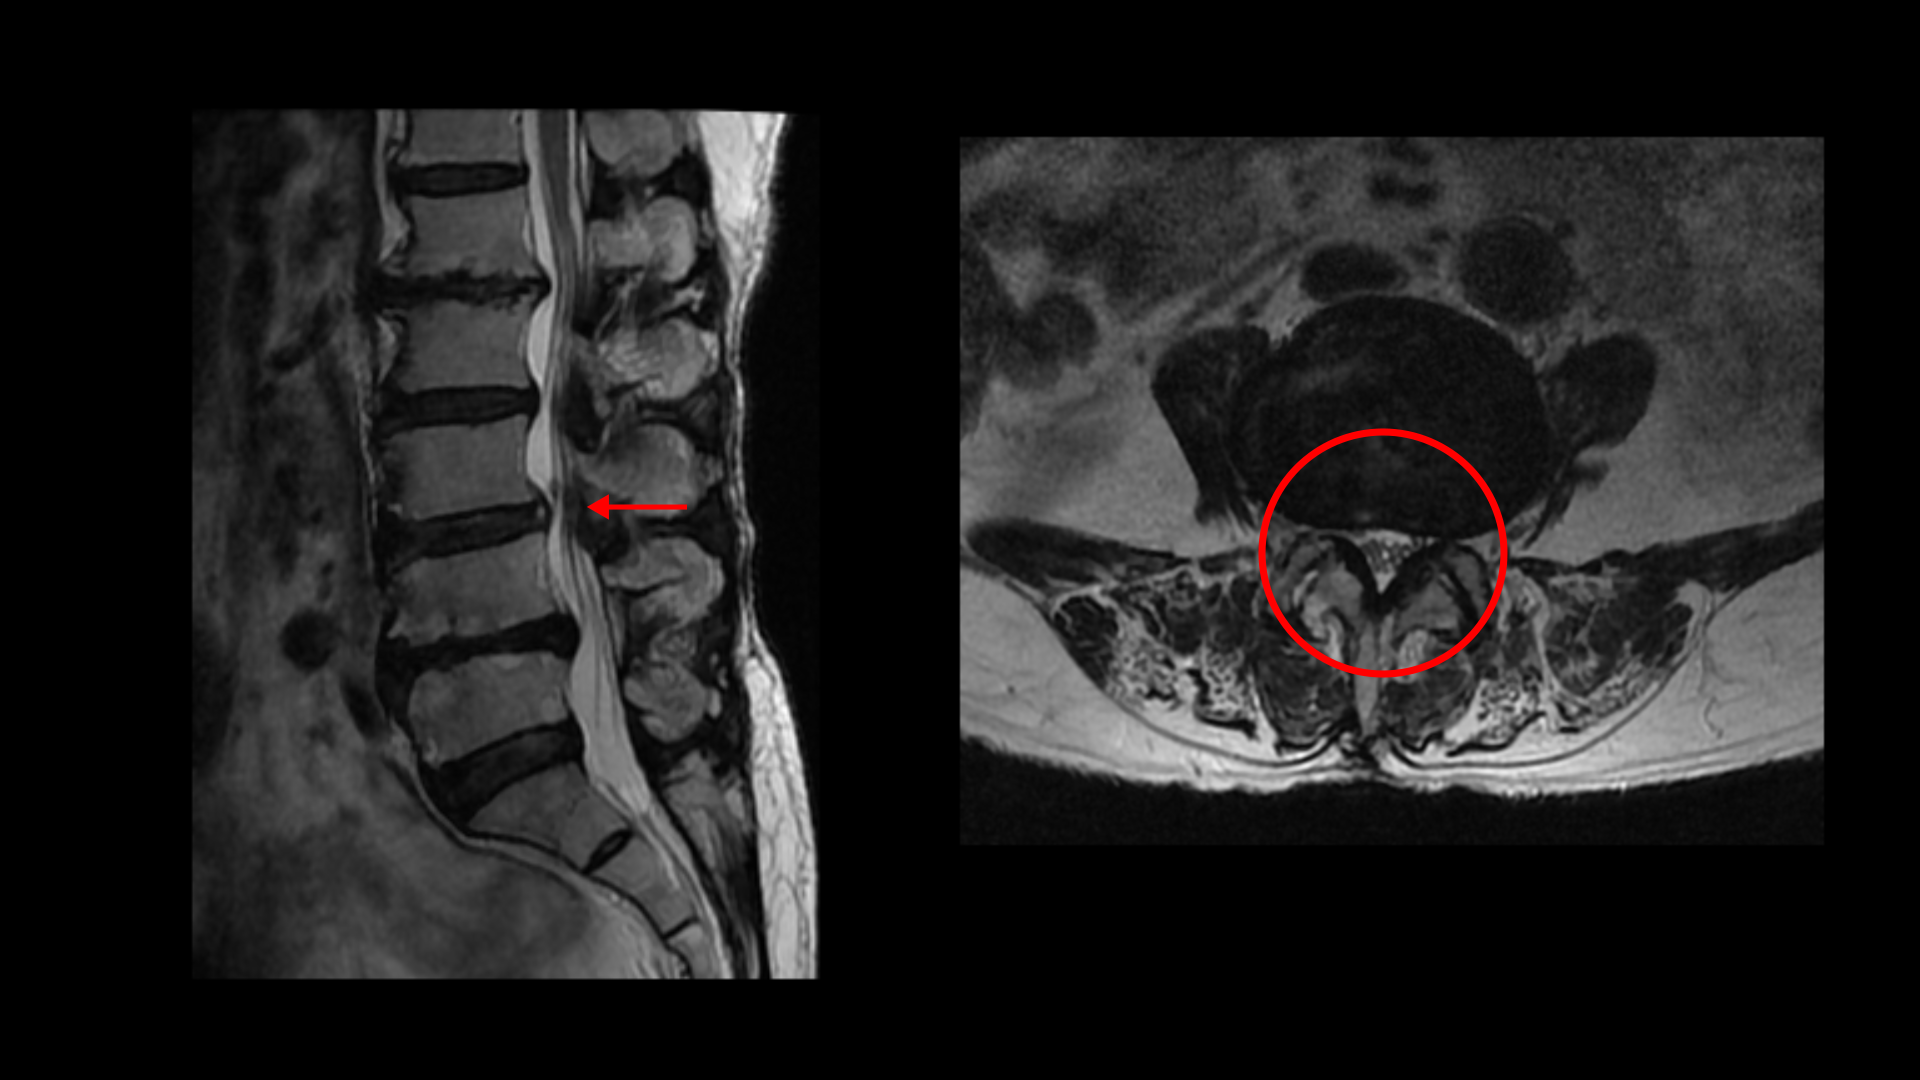

이분 MRI를 보면 허리 다섯 마디에 전부 퇴행성 디스크가 있습니다.

3-4번에는 중심성 협착이 있고

4-5번에는 왼쪽으로 디스크가 밀려 나와있고 심한 중심성 협착과 왼쪽 추간공협착도 있습니다.